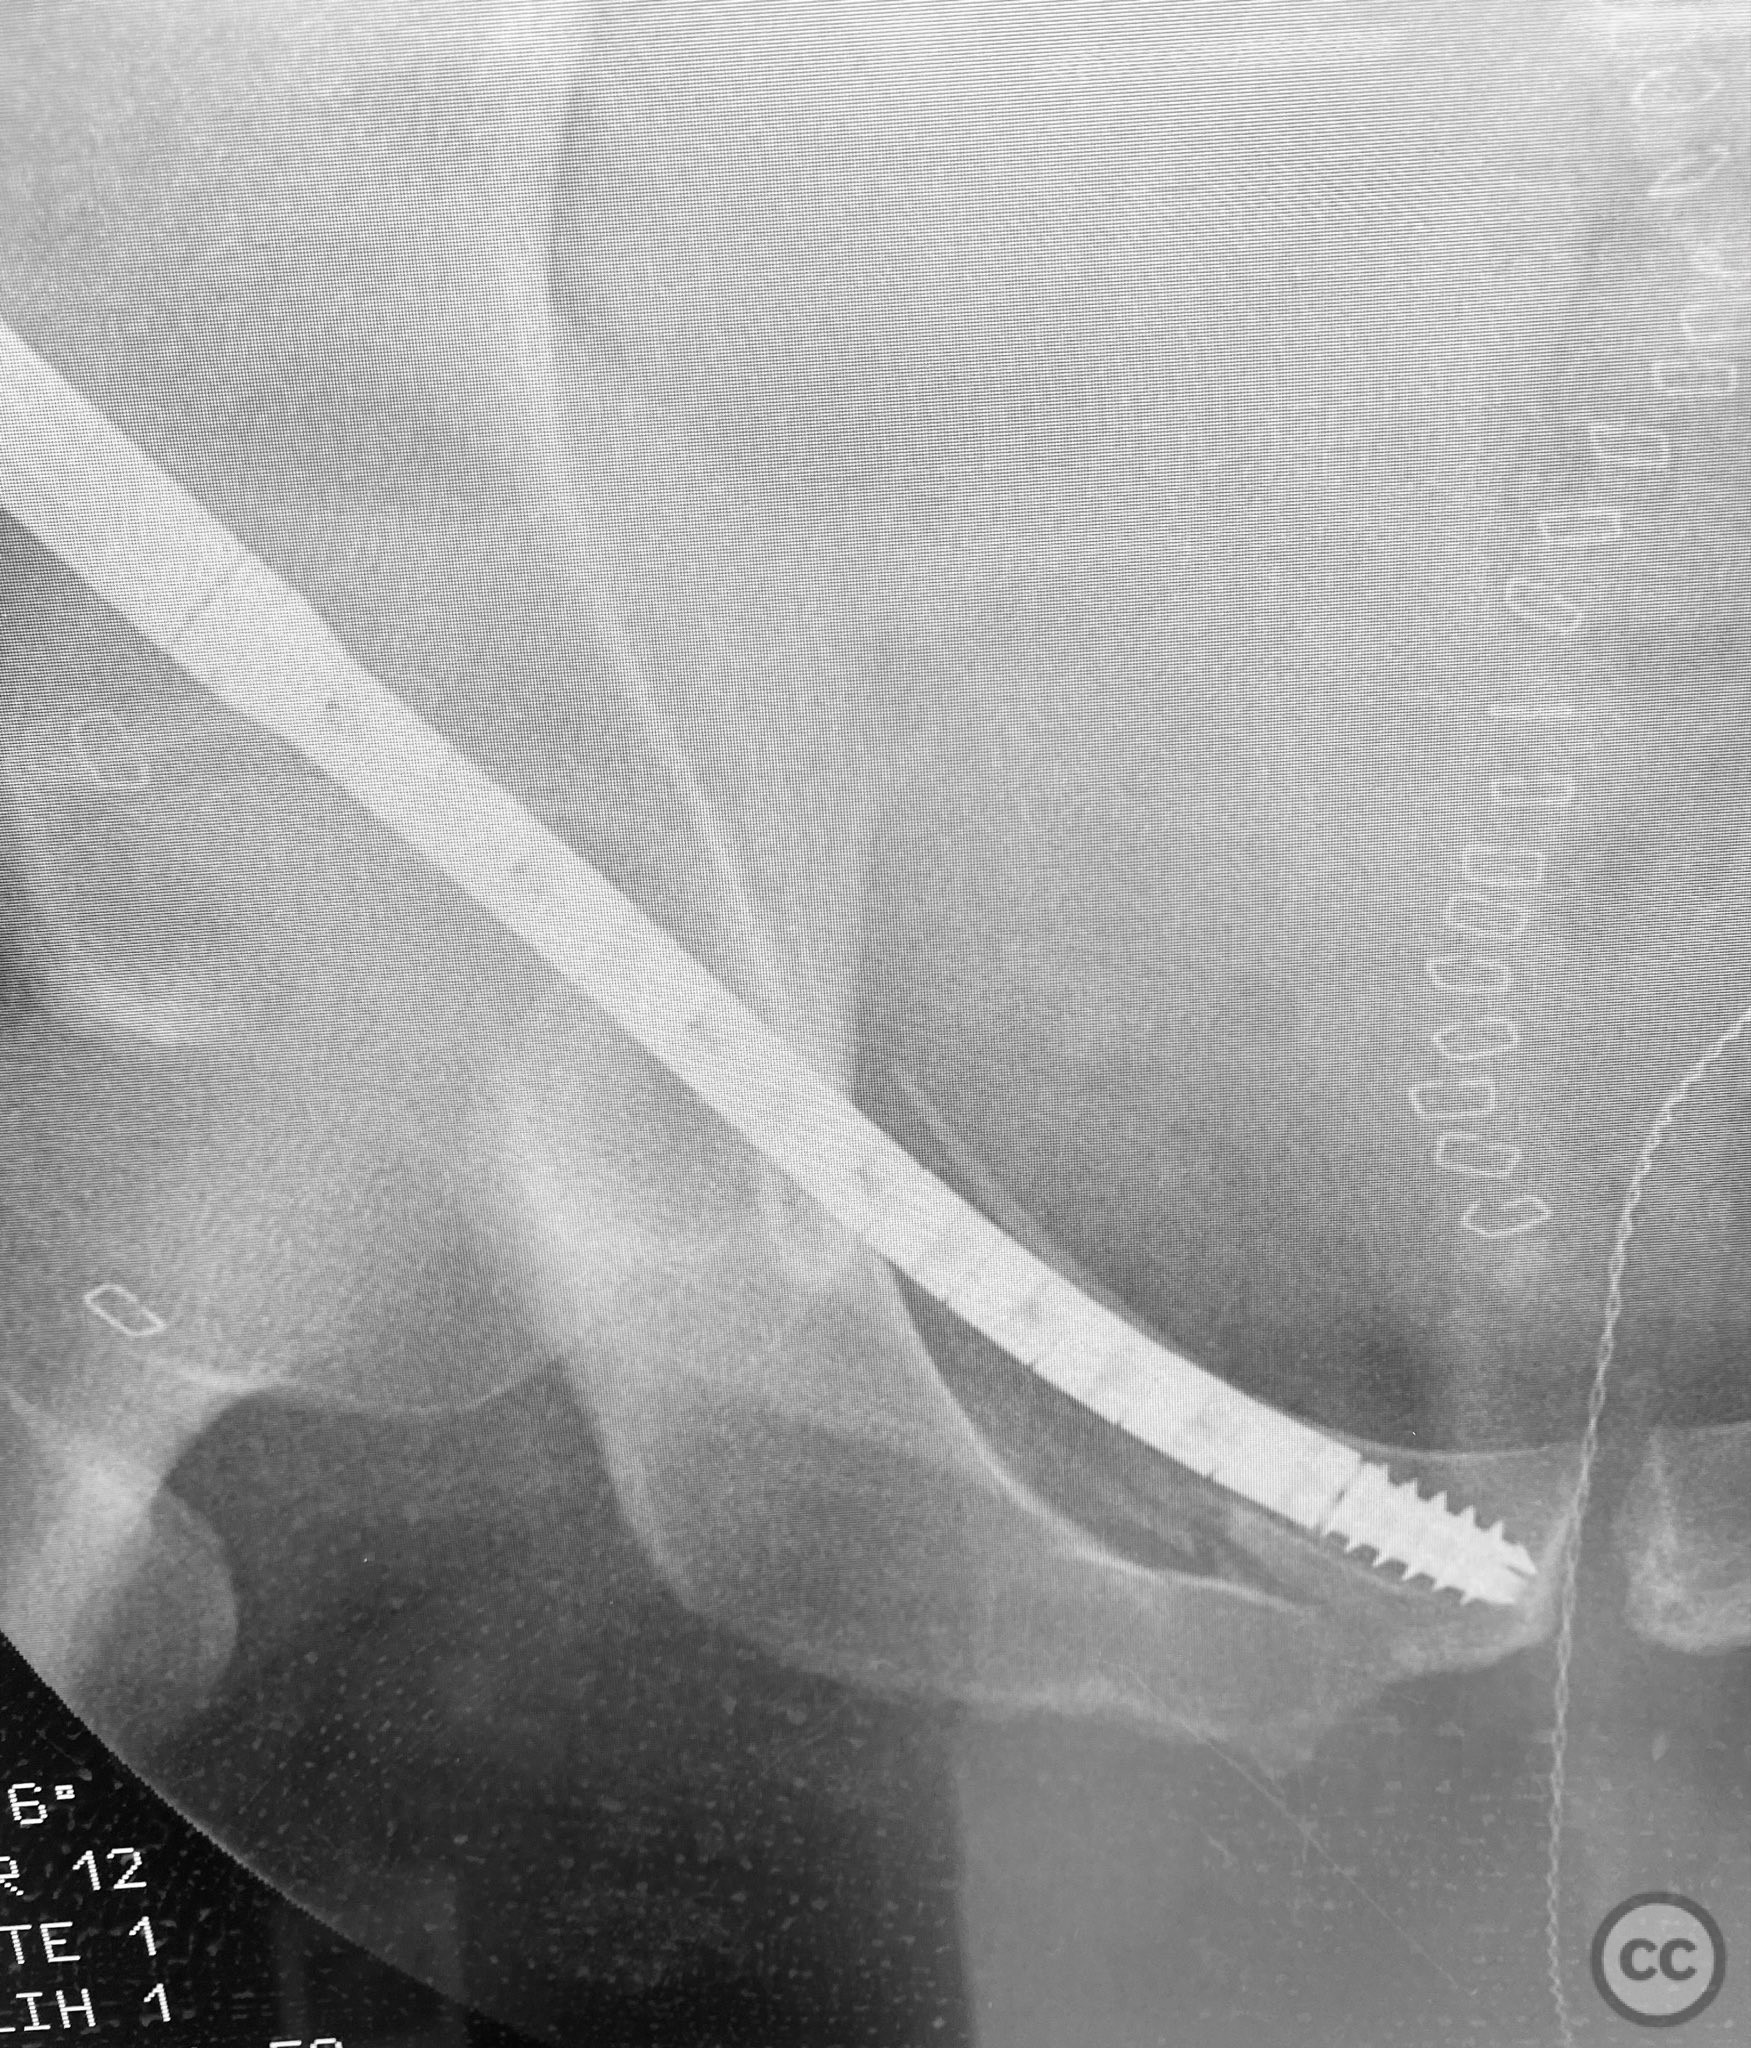

Clinical and radiological findings:  A patient sustained a high-energy lap belt injury resulting in an H-pattern sacral fracture (AO/OTA 61-C1.3) and bilateral pubic ramus fractures (AO/OTA 61-C1.3). Initial clinical assessment revealed a hemodynamically stable patient with no neurological deficit. Radiological evaluation with pelvic radiographs and computed tomography demonstrated a complete H-type sacral fracture involving both sacral ala and the central sacral body, as well as displaced bilateral superior and inferior pubic ramus fractures. No associated acetabular or hip dislocation was identified.

Planning remarks:  The preoperative plan was to achieve stabilization of the bilateral pubic ramus fractures using a 7.5mm CurvaFix medullary device, selected for its ability to conform to the curved osseous pathway of the pubic ramus. Percutaneous fixation of the sacral fracture was planned using standard iliosacral screw technique.

Anatomical surgical approach:  A percutaneous approach was utilized for the pubic ramus fixation. A small stab incision was made over the anterior aspect of the pubic tubercle. Blunt dissection was carried down to bone, and a guidewire was advanced under fluoroscopic guidance along the intramedullary canal of the superior pubic ramus, traversing the fracture site. The 7.5mm CurvaFix medullary device was then inserted over the guidewire, conforming to the osseous curvature and achieving stable fixation across the fracture. The procedure was repeated for the contralateral side. For sacral fixation, percutaneous iliosacral screws were placed under fluoroscopic guidance through small lateral incisions over the posterior ilium.

The use of the CurvaFix medullary device allowed for anatomic alignment and stable fixation of the bilateral pubic ramus fractures by accommodating the natural curvature of the osseous pathway, which is often challenging with traditional straight implants. This technique provided robust fixation in a fracture pattern that is historically difficult to stabilize, minimizing soft tissue disruption and facilitating early mobilization.

Orthopaedic implants used:   7.5mm CurvaFix Medullary Device (bilateral). Cannulated iliosacral screws.